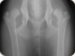

erke123 :

>va musu rytu europos aviganio rentgeno nuotraukos. idejau 5 nuotraukas gal kas matysis.